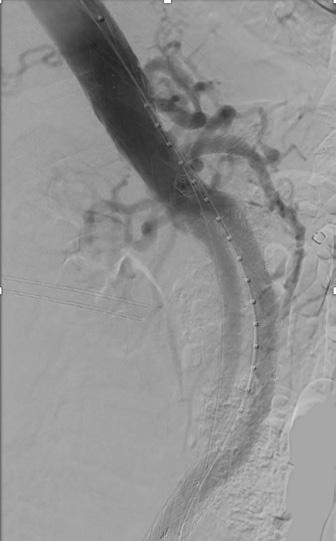

This custom endovascular device can be implanted inside the aorta to seal the aneurysm. A precise opening in the mid segment of the graft allows for blood flow into important arteries while still sealing the aorta above and below the aneurysm.

Below, the graft has been implanted with cannulation of each of the openings and wires placed into each important kidney and bowel artery to maintain blood flow.

Finally, this image shows the sealed aneurysm with continued blood flow in the visceral (kidney and intestinal) arteries.